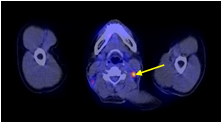

Hình 2 ghi lại kết quả chụp PET/CT của bệnh nhân Trịnh Th. T. L., nữ, 66 tuổi, gần đây thấy xuất hiện ù tai trái, hạch cổ trái. Sinh thiết hạch cổ trái là ung thư biểu mô di căn hạch chưa rõ nguyên phát. Bệnh nhân được chỉ định chụp PET/CT để tìm ổ ung thư nguyên phát.

Hình 2: Hình PET toàn thân và hình PET/CT thấy tổn thương ở vùng vòm (mũi tên đỏ) và hạch góc hàm (mũi tên xanh) tăng hấp thu FDG. Hình ảnh hướng đến ung thư vòm di căn hạch góc hàm trái. Bệnh nhân đi nội soi và bấm sinh thiết vùng vòm trái cho kết quả ung thư biểu mô tế bào vẩy.